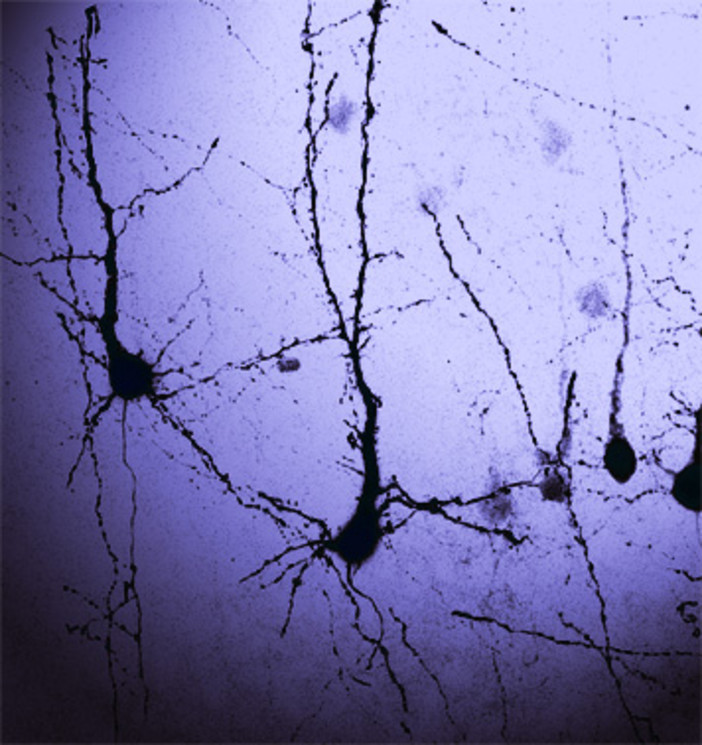

In particolare, i ricercatori si sono concentrati sull'effetto del nuovo composto chimico sulla proteina NKCC1, una proteina recentemente considerata da vari gruppi di ricerca nello sviluppo di farmaci per il trattamento dei disturbi cerebrali. NKCC1 agisce da trasportatore di ioni di cloro (e altre sostanze) all’interno del cervello, regolando la corretta concentrazione di tali ioni che è cruciale per la funzione cerebrale. In diversi condizioni cerebrali come la sindrome di Down, l'autismo e l'epilessia, la concentrazione di tali ioni nel cervello è alterata a causa della funzione anomala di NKCC1. I nuovi composti oggetto della ricerca possono bloccare NKCC1 in modo potente e selettivo, senza effetti collaterali indesiderati (diuresi eccessiva) causati in realtà da altri farmaci esistenti che sono inibitori non selettivi di NKCC1.